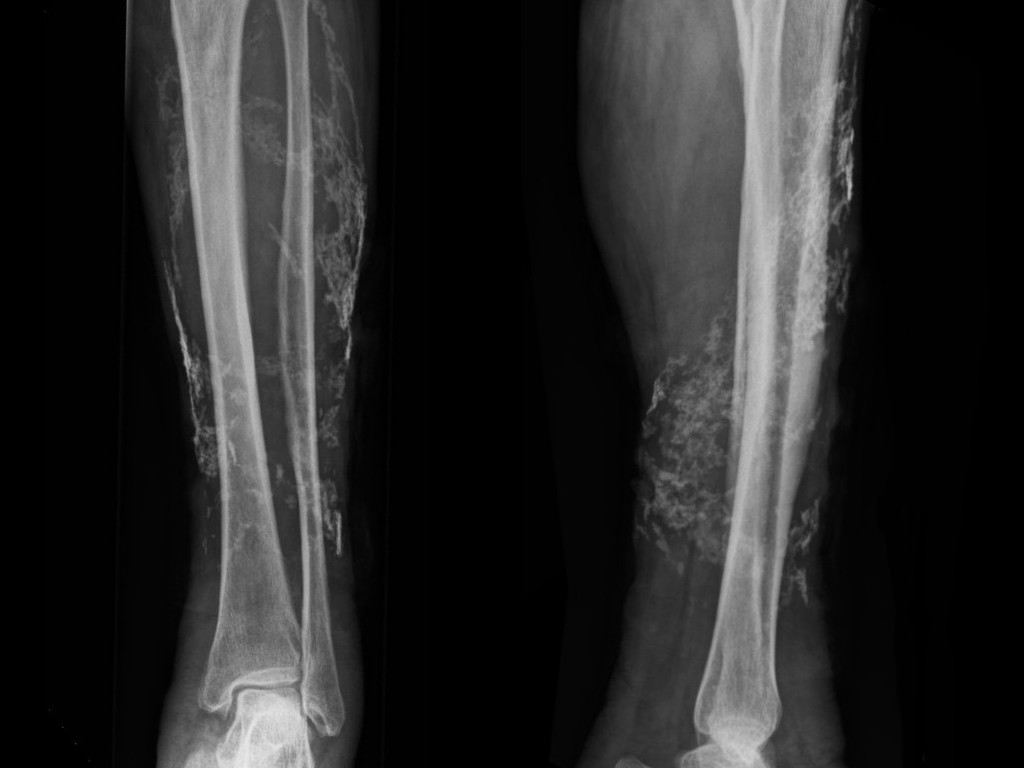

![Calcinosis cutis bij chronische veneuze insufficientie (click on photo to enlarge) [source: www.huidziekten.nl] Calcinosis cutis bij chronische veneuze insufficientie](../../../images/calcinosis-cutis-1z.jpg) |

![Calcinosis cutis bij chronische veneuze insufficientie (click on photo to enlarge) [source: www.huidziekten.nl] Calcinosis cutis bij chronische veneuze insufficientie](../../../images/calcinosis-cutis-2z.jpg) |

![Calcinosis cutis bij chronische veneuze insufficientie (click on photo to enlarge) [source: www.huidziekten.nl] Calcinosis cutis bij chronische veneuze insufficientie](../../../images/calcinosis-cutis-3z.jpg) |

| calcinosis cutis bij CVI |

calcinosis cutis bij CVI |